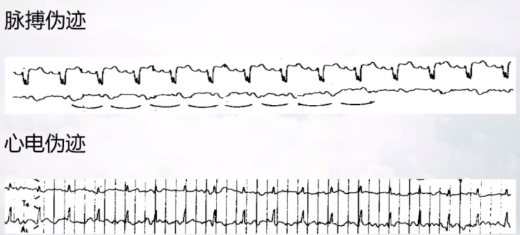

血管性伪迹至少包括两种:

心电伪迹

一般做睡眠脑电时,容易产生心电伪迹。解决办法:寻找舒适的体位。注意不要将参考电极放在血管上面,将比长的线用胶带粘到帽子上。